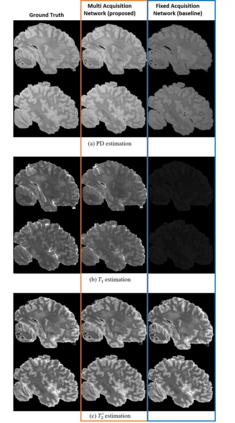

In neuroimaging, MRI tissue properties characterize underlying neurobiology, provide quantitative biomarkers for neurological disease detection and analysis, and can be used to synthesize arbitrary MRI contrasts. Estimating tissue properties from a single scan session using a protocol available on all clinical scanners promises to reduce scan time and cost, enable quantitative analysis in routine clinical scans and provide scan-independent biomarkers of disease. However, existing tissue properties estimation methods - most often $\mathbf{T_1}$ relaxation, $\mathbf{T_2^*}$ relaxation, and proton density ($\mathbf{PD}$) - require data from multiple scan sessions and cannot estimate all properties from a single clinically available MRI protocol such as the multiecho MRI scan. In addition, the widespread use of non-standard acquisition parameters across clinical imaging sites require estimation methods that can generalize across varying scanner parameters. However, existing learning methods are acquisition protocol specific and cannot estimate from heterogenous clinical data from different imaging sites. In this work we propose an unsupervised deep-learning strategy that employs MRI physics to estimate all three tissue properties from a single multiecho MRI scan session, and generalizes across varying acquisition parameters. The proposed strategy optimizes accurate synthesis of new MRI contrasts from estimated latent tissue properties, enabling unsupervised training, we also employ random acquisition parameters during training to achieve acquisition generalization. We provide the first demonstration of estimating all tissue properties from a single multiecho scan session. We demonstrate improved accuracy and generalizability for tissue property estimation and MRI synthesis.